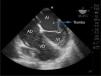

Describimos un caso de trombosis cardíaca intraoperatoria durante una cirugía de trasplante ortotópico hepático que derivó en muerte intraoperatoria. Mediante ecocardiografía transesofágica, colocada durante la descompensación del paciente, se pudo determinar la causa del problema y observar con precisión el mecanismo de migración de trombos desde la circulación venosa hacia el corazón izquierdo.

We describe a case of intraoperative cardiac trombosis during orthotopic liver transplant surgery that resulted in intraoperative death. By using transesophageal echocardiography, the cause of the descompensation of the patient could be determined and the mechanism of trombus migration from thrombi from the venous circulation to the left heart was accurately observed.